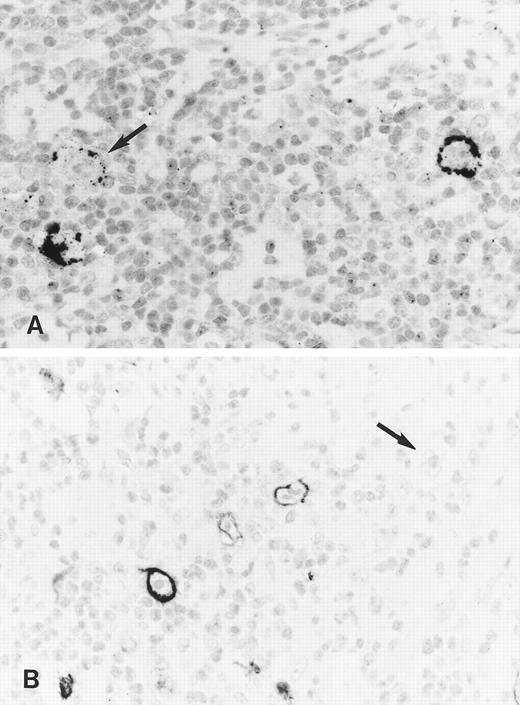

Immunohistology shows expression of LMP2A in HRS cells of two further cases of ns HD using the MoAbs 4E11 (A) and 15F9 (B). Note patchy staining of some HRS cells (arrow in A) in the first case and the absence of detectable LMP2A in some tumor cells of the second case (arrow in B).

Staining with both MoAbs resulted in a crisp membrane staining of HRS cells. This was often patchy with parts of the membrane remaining unstained and appeared granular in some cases (Figs 3A and B and 4). Focal dot-like staining of the Golgi region was also occasionally observed, similar to the pattern seen with LMP1-specific MoAbs. The staining intensity varied between cases and between HRS cells within individual cases and some HRS cells remained unlabeled in all cases (Fig 4B). The proportion of HRS cells expressing LMP2A was estimated by comparison with sections stained with the LMP1-specific and the CD30-specific MoAbs. This showed that between less than 5% and up to 60% of the neoplastic cells showed detectable LMP2A expression. LMP2A immunostaining followed by EBER in situ hybridization in one case confirmed that LMP2A expression was confined to the EBER-positive tumor cells (Fig 3C). Nineteen cases from the United Kingdom and 20 cases from Hamburg were EBV-negative. Thirty-six of these showed no labeling of the HRS cells. In 2 cases from the United Kingdom and in one from Hamburg, strong diffuse cytoplasmic staining of most HRS cells was observed (Table 1). This staining pattern differed from the membrane staining observed in the EBV-positive cases and was considered nonspecific.